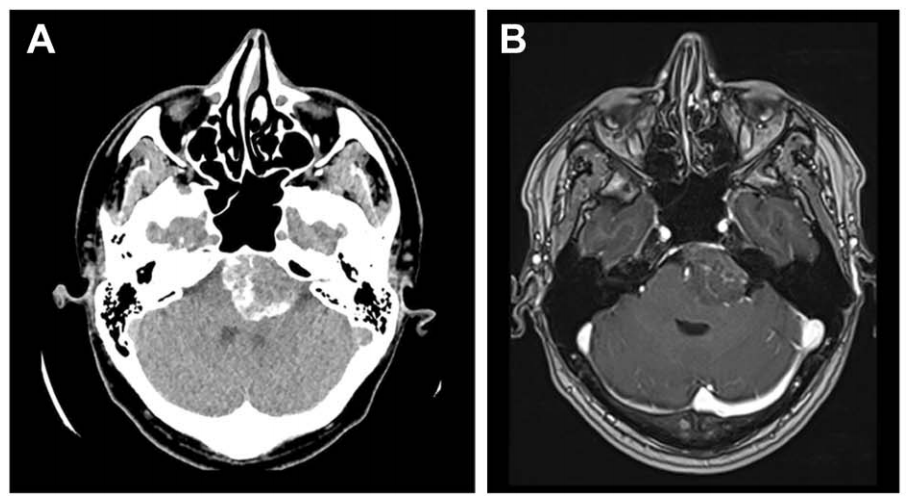

生活中头痛很常见,33岁的诺亚总感觉后脑勺隐隐作痛,起初他以为只是工作太累,直到疼痛越来越频繁,才不得不去医院检查。当CT结果出来的那一刻,都震惊了——他的颅底岩斜区竟然藏着一个足足有4厘米大的脑膜瘤!这个“不速之客”挤压脑桥,但无继发性脑积水,仅仅普通头痛,让人防不胜防。

诺亚术前影像,左侧岩斜区脑膜瘤,呈不均匀强化。

而诺亚的肿瘤CT上看是个后颅窝硬膜外钙化病灶,核磁上表现为左侧岩斜区一个占位性病变,向后压迫脑干,所以福教授选择经鼻内镜手术——兵分两路:先通过血管栓塞术切断肿瘤的"粮草供应",再采用先进的单鼻孔内镜技术精准切除。

具体分析:由于已知该肿瘤的血供丰富,福教授在手术前进行了DSA检查,显示其供血动脉主要为咽升动脉及脑膜垂体干。

诺亚术前栓塞咽升动脉及脑膜垂体干